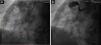

Single-plane fluoroscopy (Figure 1A) and coronary angiography showed a giant calcified aneurysm (73 mm×72 mm) of the mid-right coronary artery (RCA), and smaller aneurysms that were proximal and distal to the first. The proximal RCA was occluded by a thrombus (Figure 1B) so percutaneous revascularization could not be performed. The left coronary artery had multiple calcified aneurysms, and severe stenosis of the proximal anterior descending coronary artery (Figures 2A–C) was found. We performed ascending aortography, which was normal. These findings could be related to Kawasaki disease (KD). Despite good evolution following cardiogenic shock, the patient had upper gastrointestinal bleeding, a major and acute complication, which was fatal.